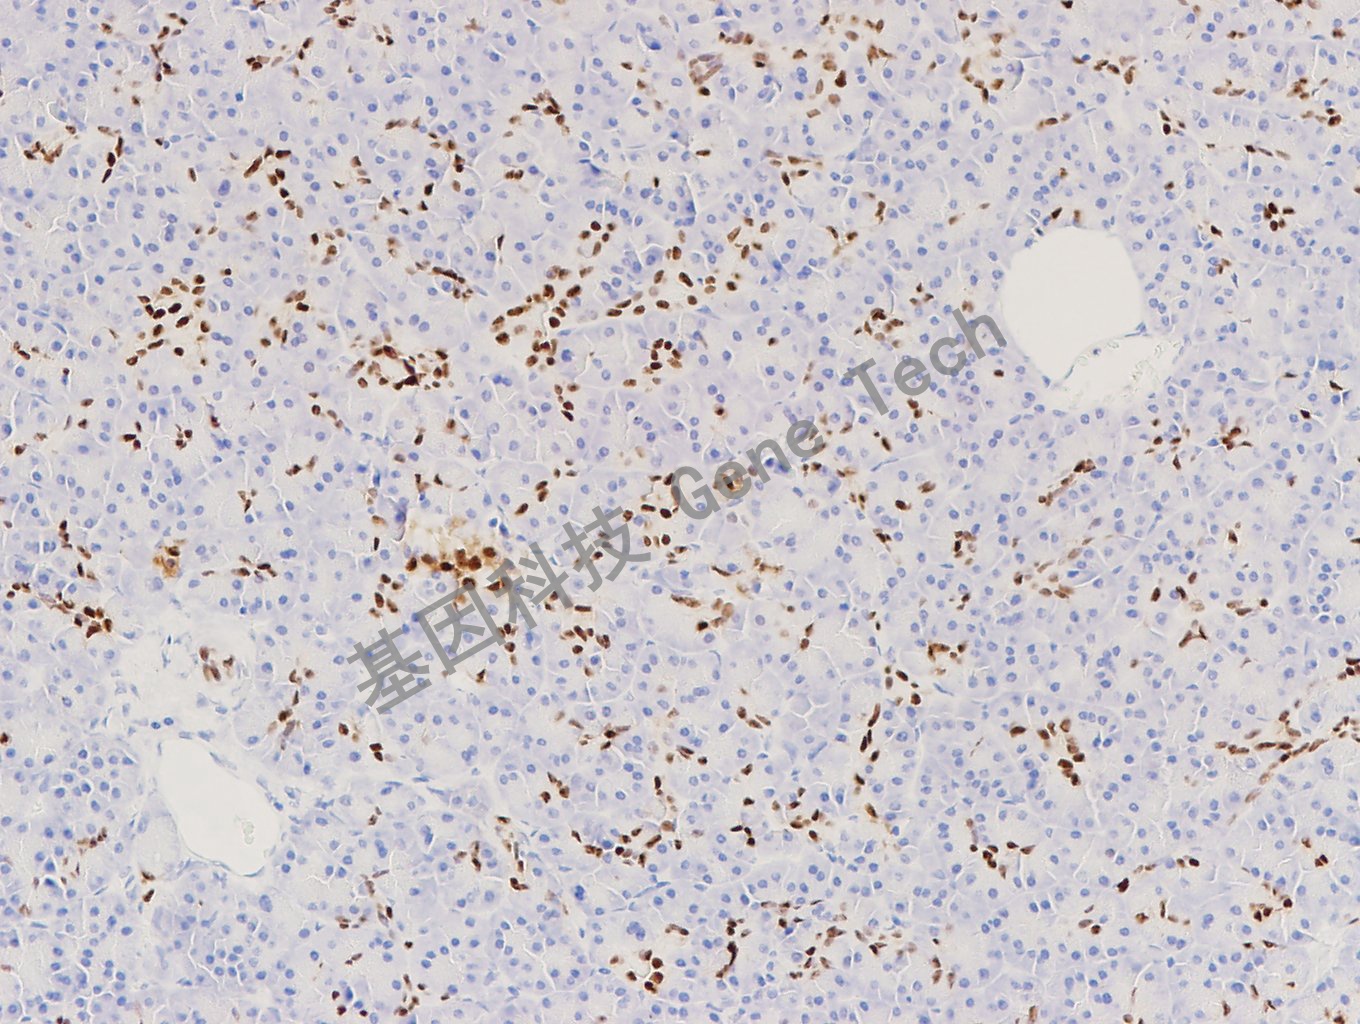

| 預(yù)處理:高pH熱修復(fù) | 陽性部位:細(xì)胞核 | 陽性對照:胰腺 |

| 胰腺石蠟切片,用 PDX1(GT2293)染色,細(xì)胞核陽性,DAB 顯色。 | ||